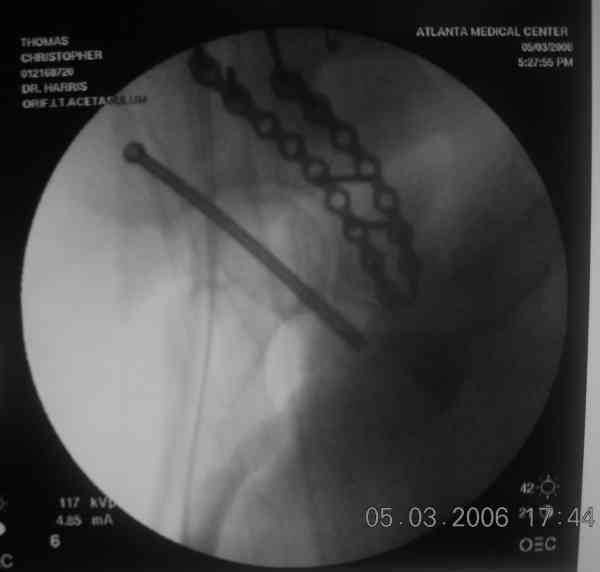

the case that I found is a 20yo male, MCC. his AP pelvis shows an interesting position of his bladder. it is pushed aside by a hematoma from SGA injury. we did a limited lateral window approach for the anterior column first, pt bumped up/supine. then closed and repositioned for KL. I could not find intra-op photos of cases when we did only a small incision for the AC screw (but they do exist!!). the lateral window is available for reduction assessment if a KL approach is being used. in the lateral position this window is available. the prone position definitely takes pressure off of the post column and facilitates reduction. in the lateral position a schantz pin in the ischial tub +/- bone hook in sciatic notch helps with PC reduction. the lateral position also gives better airway access for anesthesia. airway problems are rare, but prone position seems to be a bit more of a challenge to exchange the tube, or reintubate altogether. just something further to debate!